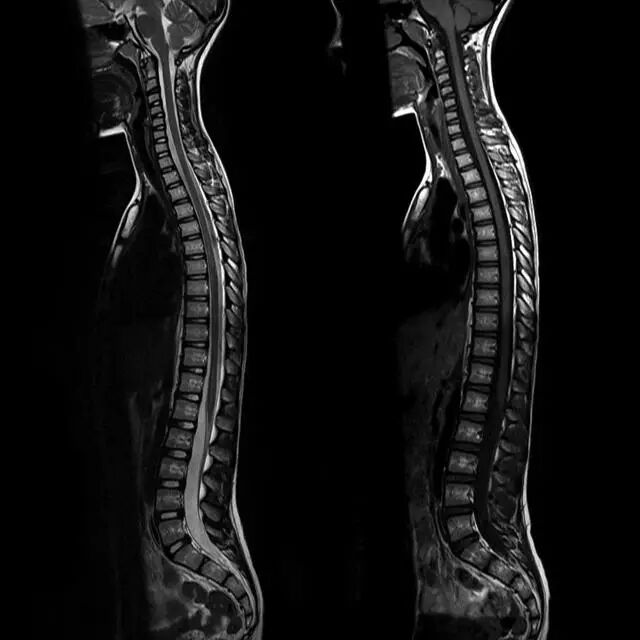

图1正常脊椎的MRI检查,左图为正中矢状位T2WI,右图为T1WI图 2 胸椎 T2WI 轴位图:1,肋椎关节;2,类骨头;3,黄韧带;4,椎弓根;5,椎弓板;6,横突;7,棘突;8,肋横突关节;9,肋结节;10,半奇静脉;11,后纵韧带图 3 腰椎矢状位 T1WI 序列成像:1,脊髓;2,脊髓圆锥;3,马尾;4,蛛网膜下腔;5,硬膜外脂肪;6,黄韧带;7,棘间韧带;8,棘上韧带;9,椎体静脉丛;10,硬膜外静脉丛;11,硬膜外脂肪;12 主动脉图 4 L5/S1 水平轴位 T1WI 序列成像:1,腰肌;2,L5 神经根(前支);3,L5 神经根(后支);4,黄韧带;5,蛛网膜下腔;6,马尾神经根;7,小关节面;8,髂腰韧带;9,左髂外静脉;10,左髂外动脉;11,右髂外动脉;12,右髂外静脉;13,多裂肌;14,竖脊肌组图 5 腰椎旁矢状位 T1WI 序列成像:1,腰静脉;2,腰动脉;3,椎间孔静脉;4,脊神经节后根;5,椎间孔静脉;6,关节面;7,多裂肌;8,竖脊肌群;9,胸腰筋膜,后层图 6 胸椎 T1WI 序列成像:1,胸髓;2,蛛网膜下腔;3,硬膜外脂肪;4,黄韧带;5,多裂肌;6,棘突;7,硬膜外静脉;8,棘上韧带图 7 胸椎矢状位 T2WI 序列成像:1,胸髓;2,蛛网膜下腔;3,黄韧带;4,多裂肌;5,棘突;6,棘上韧带;7,椎体静脉;8,脊髓圆锥;9,马尾图 8 胸椎旁矢状位 T2WI 序列成像:1,硬膜囊后壁;2,硬膜外脂肪;3,黄韧带图 9 胸椎轴位 T2WI 序列成像:1,主动脉;2,半奇静脉;3,奇静脉;4,椎间孔静脉;5,胸肋间血管;6,脊神经节后根;7,椎体静脉;8,后纵韧带;9,脑脊液流动伪影;10,多裂肌;11,背最长肌;12,斜方肌图10 胸椎旁矢状位 T2WI 序列成像:1,椎间孔静脉;2,胸椎旁肋间动静脉;3,神经根;4,上关节突;5,下关节突;6,关节面;7,椎弓峡部;8,椎弓根;9,黄韧带;10,竖脊肌群;11,斜方肌——本期完——